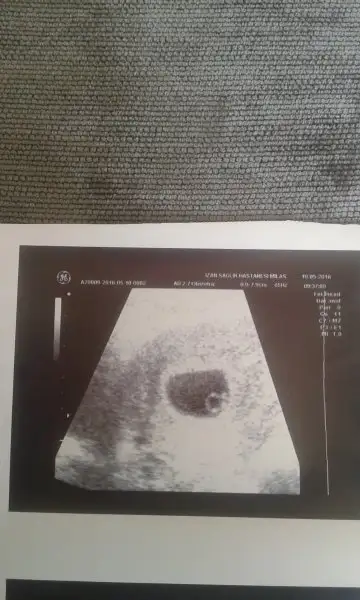

kız :) hem kese hemde bebeğin konumu yüksek ihtimal kız gibi. tabi ki yanılma payı da var. Rabbim bilir doğrusunuArkadaslar 8 haftalik usg goruntusu tahminde bulunabilirmisiniz ?

6+2 karından ultrason :)